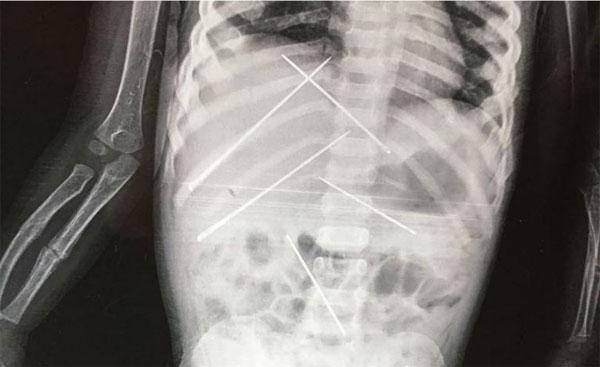

Dị vật bên trong cơ thể bé gái. Ảnh: SWNS.

Tại đây, em được bác sĩ phát hiện bị thương quanh vùng kín, có dấu hiện của sự xâm hại tình dục. Đồng thời, kết quả chụp chiếu cho thấy bên trong cơ thể cô bé có chứa các dị vật bằng kim loại.

Hôm 18/7, sau khi sức khỏe hồi phục, các bác sĩ đã phẫu thuật lấy ra 7 chiếc kim có độ dài 5 cm từ người bé gái. Tuy nhiên, 3 ngày sau em tử vong do nhiễm khuẩn máu và viêm phổi. “Cô bé đã qua đời do nhiễm khuẩn huyết và viêm phổi vào 2h sáng 21/7”.